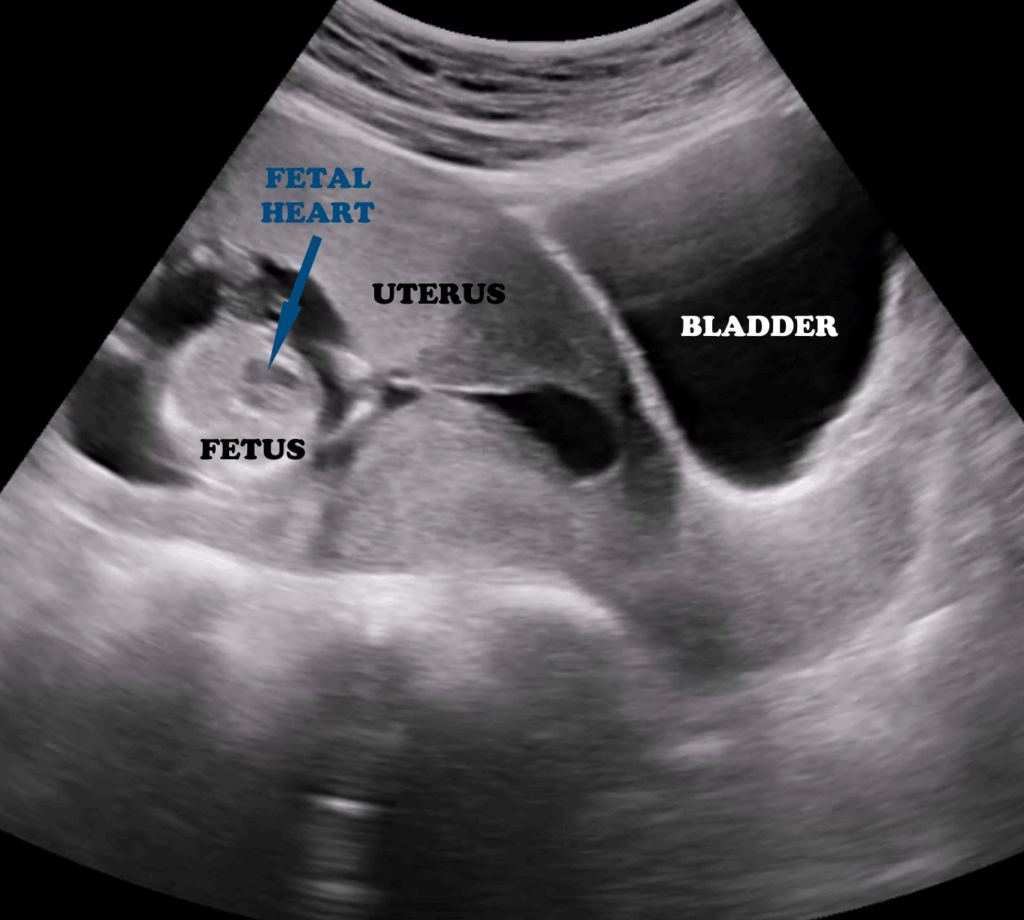

The bladder lumen appears anechoic, while the walls are smooth and hypoechoic (Figure 18).In female patients, pelvic ultrasound also includes the evaluation of the uterus and ovaries (Figure 18). The uterus is recognized by its characteristic “double line” appearance, and in pregnancy, the embryo may be visualized (Figure 19).